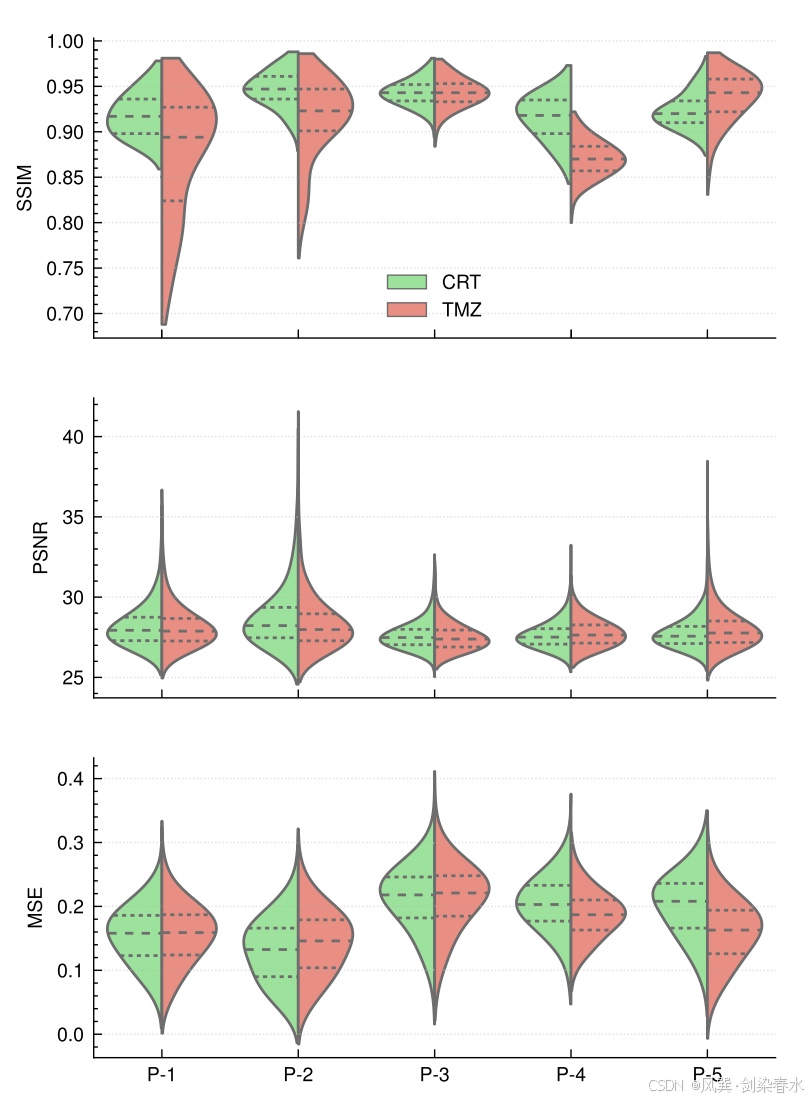

Figure 4 | 三个分割的小提琴图比较了每个治疗(CRT和TMZ)对所有患者 MRI 生成指标的分布:虚线表示每个组的四分位数。值得注意的是,对于患者 P-1 和 P-2 ,TMZ 在 SSIM 指标下的第一个四分位数以下呈现出长尾分布。主要原因在于 P-1 在使用 TMZ 期间接受了第二次手术治疗,而 P-2 被诊断为继发性胶质母细胞瘤;